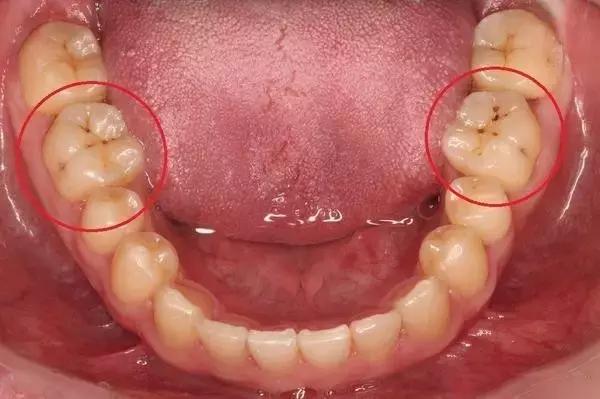

龋齿(蛀牙)发展三部曲:

浅龋:细菌只附在牙釉质层,初期表现为牙釉质面上有褐色或黑褐色的斑块,一般无症状,在检查时下被发现。

中龋:细菌已经攻到牙本质层了,这种情况下,有可能一开始会感觉到酸痛,但是过一段时间就慢慢没那么明显了。

深龋:细菌攻破牙本质快接近牙髓的时候,就比较严重了,一般遇到冷热酸甜都是很酸痛或刺痛。严重的还会扩散到牙周,引发牙周感染。